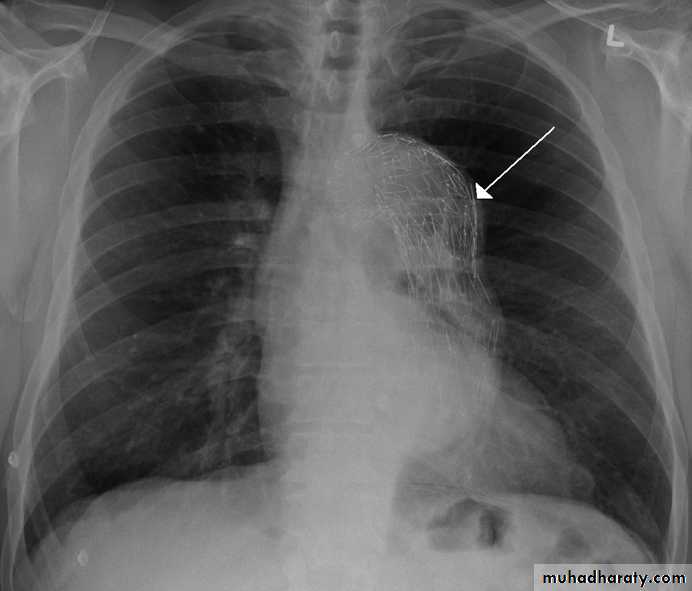

Massive pleural effusion with mediastinal shift to the left.

(A) Chest radiograph(B) CT coronal reconstruction. A massive effusion displaces the mediastinum to the left. CT shows the important pleural effusion together with the enhanced atelectatic left lung.

Note also the depression of the right hemidiaphragm (arrows).